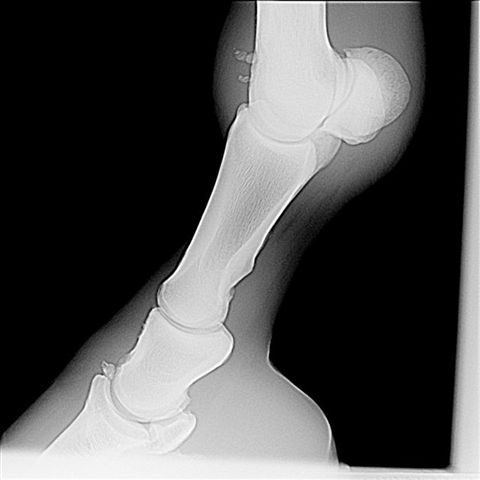

LF obl med lat

The horse has remarkable bone fragments in the coffin, pastern, and fetlock joints. All appear to be osteochonDrOsis type fragments. While no one can predict the future the severity of the lesions suggest a high likely hood of developing osteoarthritis in these joints. Surgery to remove the fragments will improve the prognosis but the multijoint nature and severity of the lesions still would have a guarded prognosis in my judgement.